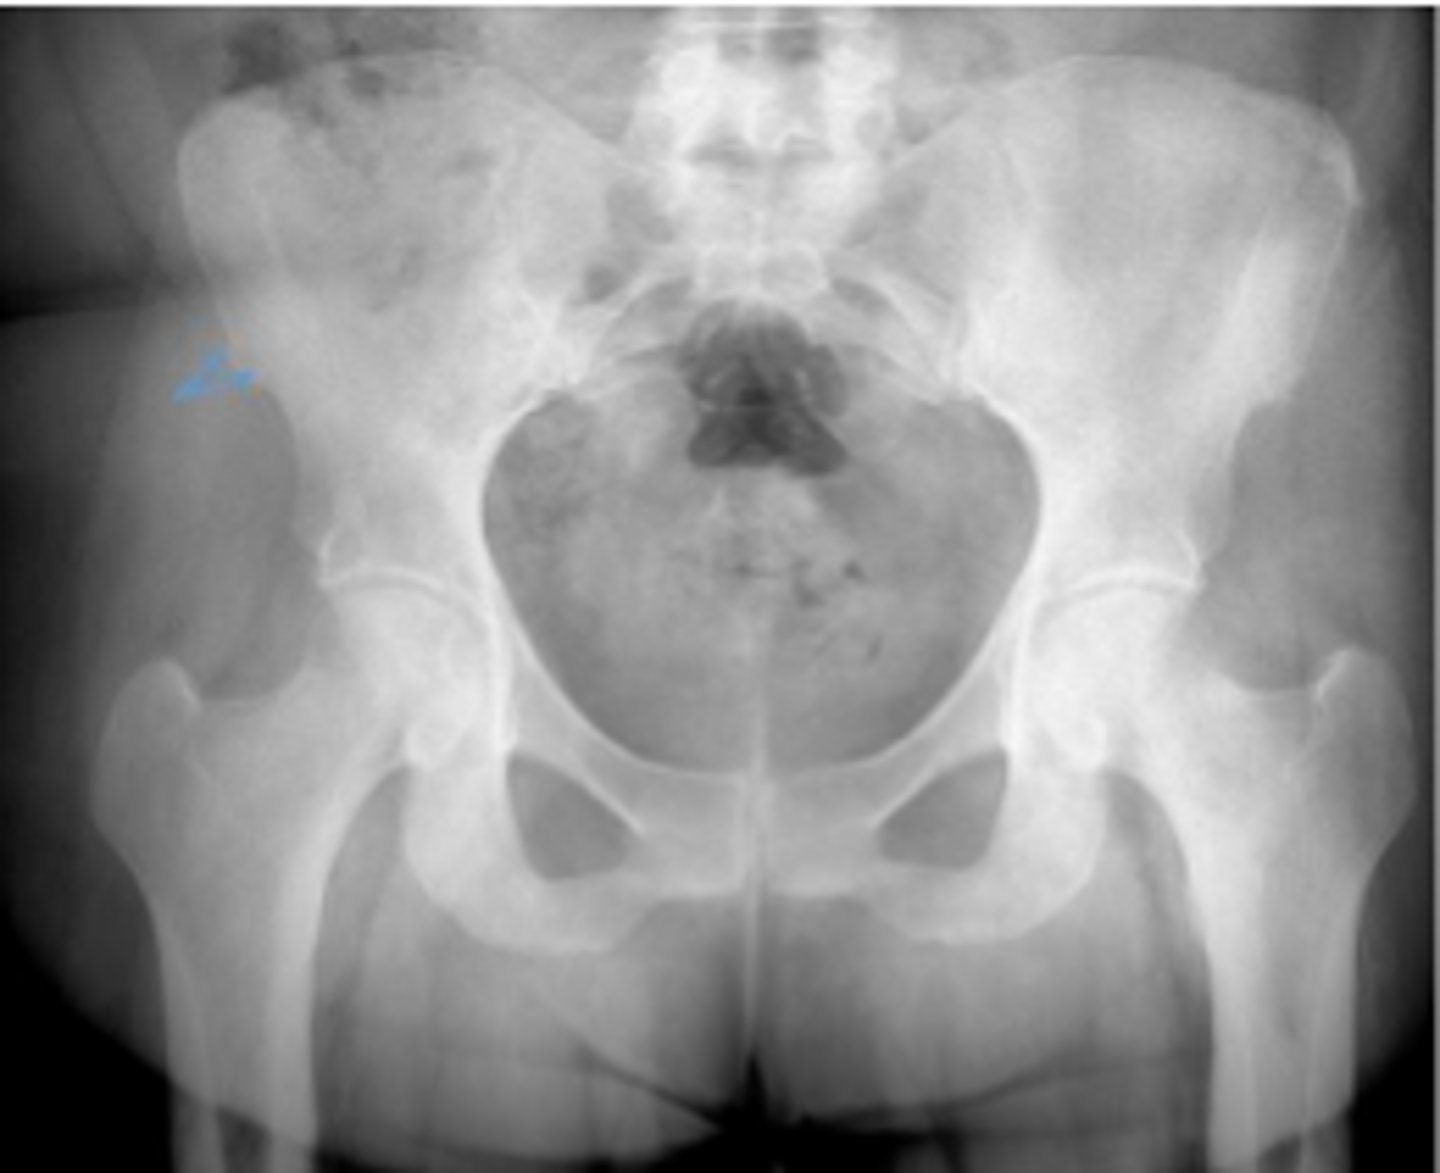

AP pelvis or bilateral hips

What is the name of the radiographic view?

Iliac crest

What are the arrows pointing to?